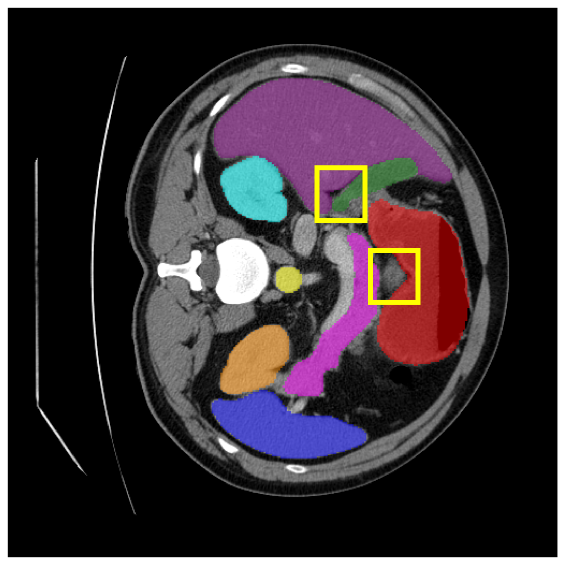

4.3.2 Visual Comparisons

Visualization of our method on the Synapse and ACDC datasets is shown in Fig. 3(a) and Fig. 3(b). For the Synapse dataset illustrated in Fig. 3(a), FCT failed to accurately segment SM and GB, while MERIT achieved precise segmentation of SM but struggled with GB. In contrast, our method achieved accurate segmentation of both SM and GB. Regarding the ACDC dataset shown in Fig. 3(b), while previous methods achieve comparable segmentation of the Myo and LV to the GT, they exhibit noticeable errors on the RV, including invasion into adjacent organs and misrecognition. On the other hand, our method accurately segments across all three structures Myo, LV, and RV, performing as precisely as the GT. We demonstrate the superiority of our method quantitatively and qualitatively.

To demonstrate the superiority of our method, additional qualitative comparison results for the ACDC and Synapse datasets are presented in Fig. 6, Fig. 7, respectively. Notably, in the case of GB, the quantitative results in Fig. 7 show relatively lower performance in ‘only ’. However, the visualization results in Fig. 7 reveal instances where the enhanced images identified GB regions that the original images failed to segment, albeit with some boundary over-segmentation. In such scenarios, our proposed method successfully leveraged the information from enhanced images to achieve more accurate GB segmentation. Note that this finding underscores the fact that even when quantitative performance metrics appear lower, the additional information provided by enhanced images can be valuable in the actual segmentation process.